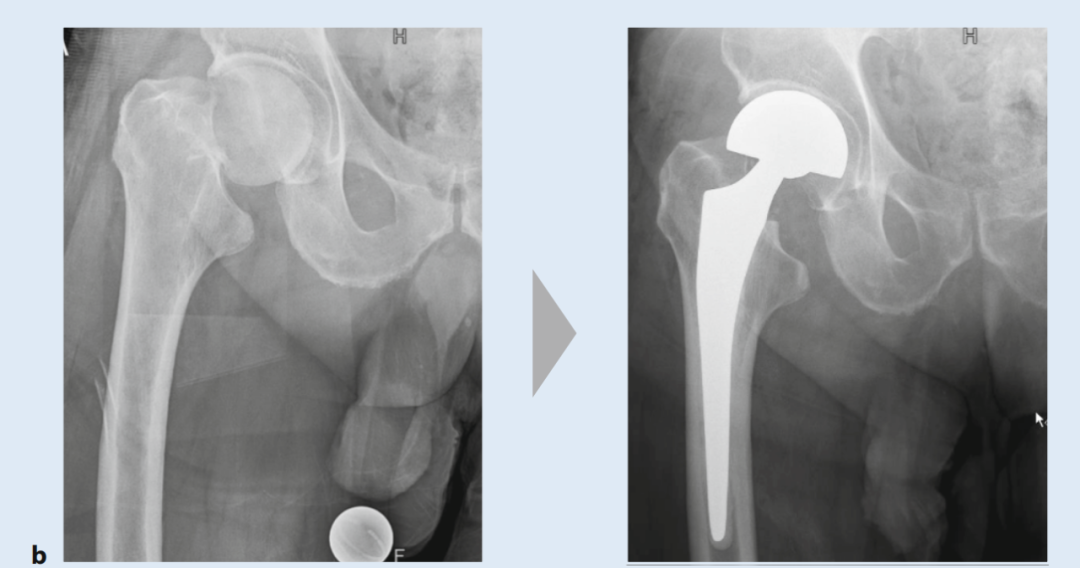

对于无移位股骨颈骨折,由于存在继发性移位风险以及需要数周制动,通常也建议手术治疗(图4)。根据一项荟萃分析的结果,绝大多数无移位骨折患者也能从手术稳定中获益。接骨术后的骨性愈合率为92.6%,而保守治疗下只有68.8%的骨折能够愈合。手术治疗的坏死发生率也较低(7.7% vs. 10.3%)。麻醉方式的选择(全身麻醉 vs. 区域麻醉)似乎对术后结果没有影响。

图4. 股骨颈骨折术前术后X光片(治疗方式对比):a) 螺钉内固定术,b) 双动头置换术,c) 全髋关节置换术

全髋关节置换术

全髋关节置换术是移位股骨颈骨折(SHF)的标准治疗方式。对于年龄超过65岁且关节已有损伤的老年患者,即使是无移位骨折,也推荐早期实施全髋关节置换术。在典型老年患者群体中,死亡风险主要受年龄、男性性别、术前血红蛋白(Hb)值、美国麻醉医师协会(ASA)评分、围术期输注的浓缩红细胞数量以及既往疾病等因素影响,而与固定方式(骨水泥、非骨水泥)关系不大。除了心血管疾病和糖尿病,肾功能障碍同样会增加术后并发症和死亡率。假体置换术后SHF失败的常见原因有假体周围骨折、脱位和假体周围感染。短柄假体在股骨颈骨折治疗中的应用前景存在疑问,至少对于外侧SHF而言,因为无法保证假体在股骨距处的充分支撑。至于未来骨水泥固定技术是否会广泛应用于短柄假体,目前还不能确定,这将取决于假体类型和患者个体因素。